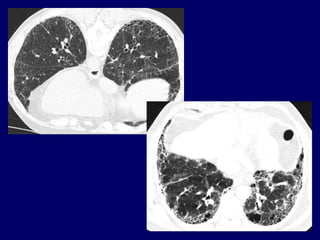

The Many ‘HRCT Faces’ of NSIP

Honeycombing not

a

prominent feature

!!!!

The Many ‘HRCTFaces’ of NSIP Honeycombing not a prominent feature !!!!